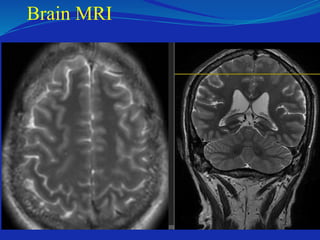

Brain MRI

Sagital C-spine MRI